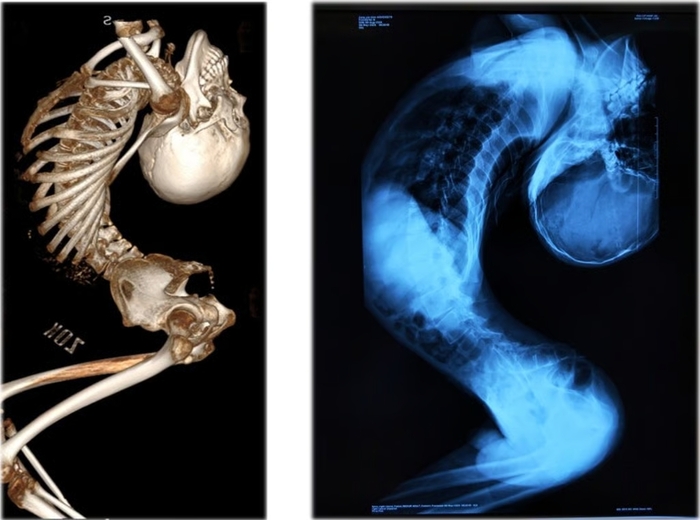

2004年、中国山東省(さんとうしょう)の小さな村で生まれたチャン・イェンチェン氏は、先天性の筋疾患により小学生の頃から首が徐々に後方へ反り、上半身がアルファベットの「Z」の形に折れ曲がっていった。脊椎が著しく後方に曲がったことで胸部と腹腔が極端に狭まり、内臓も圧迫されて健康状態は悪化し始めた。

しかし、大学入学後は症状がさらに悪化した。2023年5月には、体が折れ曲がった影響で呼吸困難に陥った。北京の大病院は、稀少な先天性筋ジストロフィーに起因する脊椎後弯変形と診断。前例のない症例であったため、確立された治療法は存在せず、治療は難航した。

2024年、脊椎奇形治療の権威、リャン・イージェン教授のもとで治療が始まり、チャン・イェンチェン氏の回復への道が開かれた。梁教授は腰椎、頚椎、股関節、胸部の骨を切除して再配置するという4回に及ぶ超難度の手術を今年6月までに実施。約180度に曲がっていた脊椎はついに真っ直ぐになり、チャン氏は毎日6時間のリハビリを続けた結果、歩行できるまでに回復した。